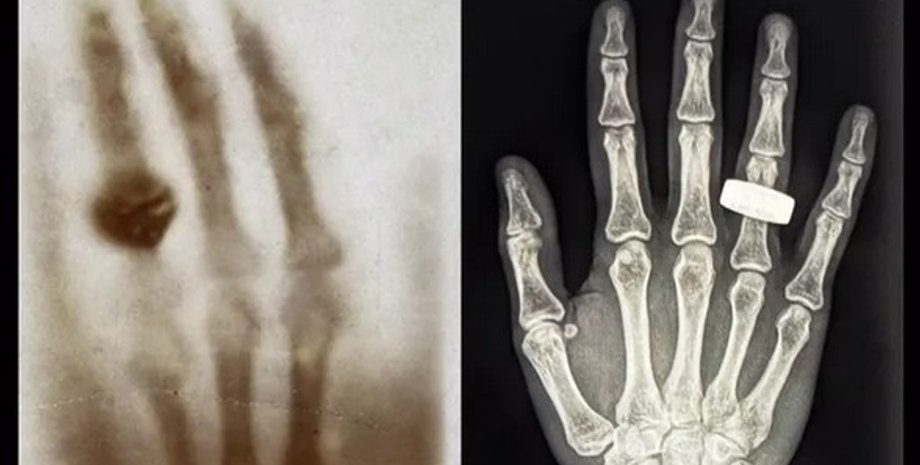

1895 року фізик Вільгельм Рентген уперше відкрив рентгенівські промені та зрозумів, що вони можуть бути корисними для медицини. У підсумку вчений зробив перший в історії рентгенівський знімок людського тіла. Це було зображення руки його дружини з обручкою. Через 130 років учасники місії Fram2 відтворили цю рентгенівську фотографію, але вже в космосі.

Перший рентгенівський знімок людини в космосі було зроблено під час місії Fram2 (праворуч). Екіпаж місії Fram2 вирішив віддати данину поваги найпершому рентгенівському знімку, на якому було зображено руку з кільцем (ліворуч)

Фото: Starship